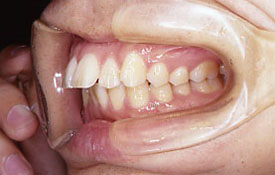

インビザラインの治療例:CASE-2

| プロフィール | 15歳 男性 |

| 所見 | アメリカから転院されて来られた方です。 インビザラインで上下顎の矯正治療を開始し下顎はアメリカで終了しており、上顎のみ治療の後期を担当しました。 アイライナーの装着は、1日平均22時間ほどでした。 |